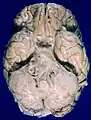

Human brain bottom view. Orbital gyri shown in red.